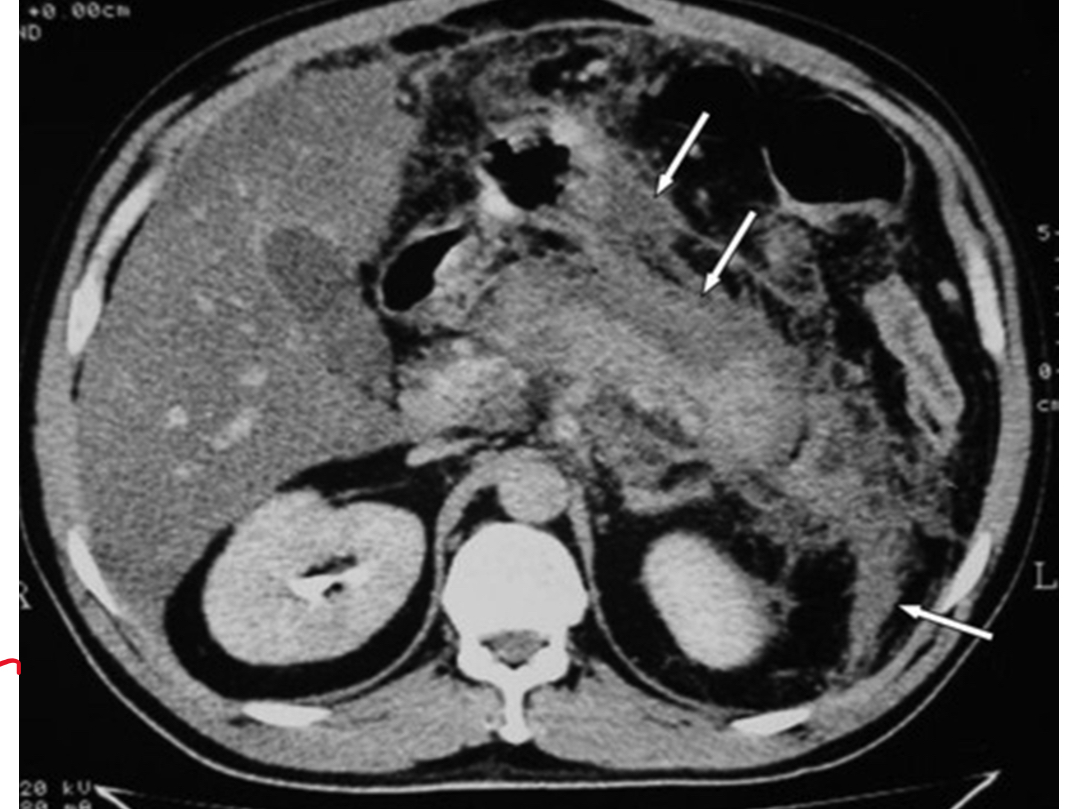

CT scan- pancreas becomes muddy *as seen on diagram *. Normally pancreas is smooth

Oedematous pancreatitis

Hameorrhagic pancreatitis - caused by arroding of blood vessels

Necrotic pancreatitis - caused by infection which can lead to infective necrosis. Bacteria produce gas in pancreas.

not ideal: very hard to distinguish on scans which is which